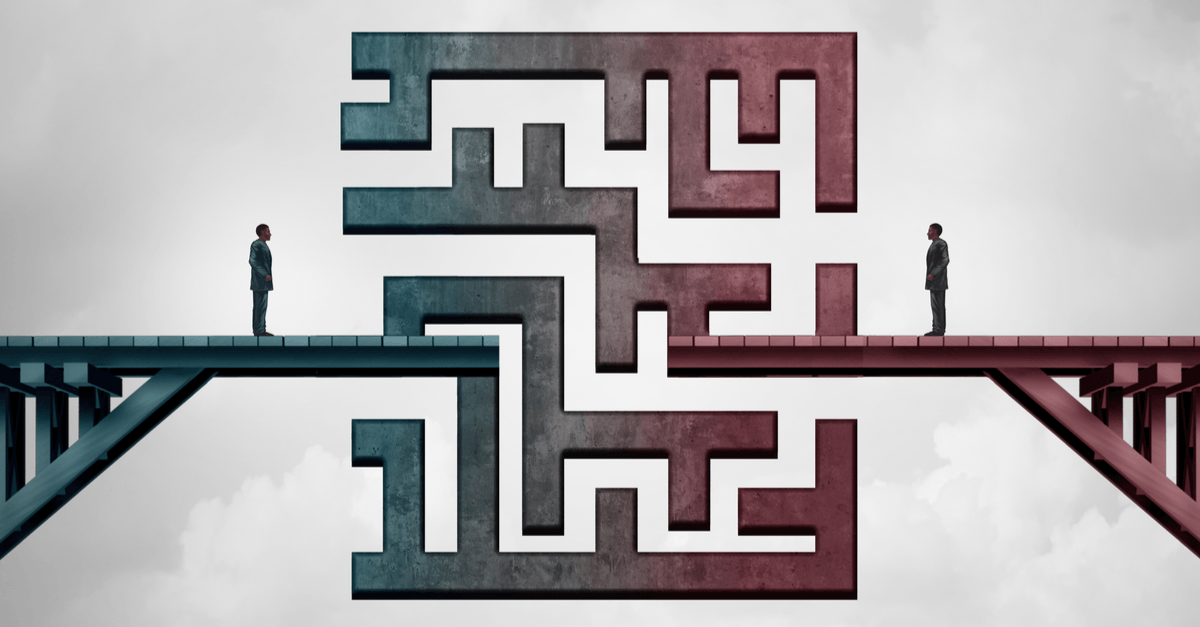

患者さん向けコンテンツの目的は、患者さんやそのご家族に疾患のことを正しく理解していただき、適切な治療に導くことです。そのためには、分かりやすい表現を用いて医療者側と受診側のコミュニケーションにありがちな「溝」を埋めることが大切です。本記事では、何気なく使っている医療者の言葉に潜む分かりにくさと、それをうまく患者さんに伝えるにはどう表現すればよいのかを解説します。

医療が、その力を最大発揮するためには、医療者と患者さんとの間できちんと情報共有がなされ、信頼関係が築かれている必要があります。ですが医療者と患者さんの間には大きな知識と経験の差が溝として立ちはだかっているのが現実です。患者さんにとっては初めての症状で、不安で夜も眠れないまま来院したのに、医療者は、それを一見して「大丈夫、命に別状はないよ」と言い切るケースがあります。それが、日常的に経験しているプロの正しい見立てだったとしても、不安でたまらない患者さんとの間にはギャップが生まれ、それが意味不明な専門用語で伝えられたら、ギャップはさらに大きく深くなるばかりです。患者さん向けコンテンツや患者さん向けサイトは、単にプロモーションにつなげるだけでなく、こういった医療コミュニケーションの溝を埋めていくハブになるような大きい役割があるのだと思います。